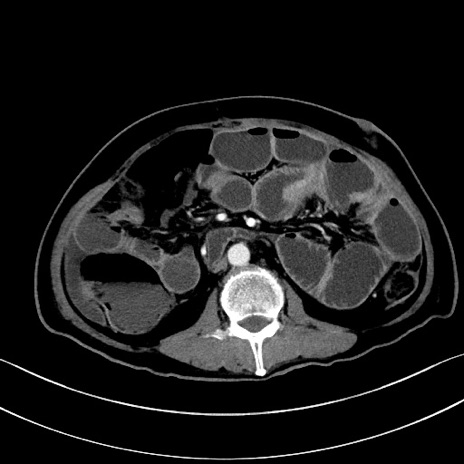

症例28(横断像)

【症例】60歳代男性

【主訴】嘔吐

【現病歴】胃癌にて胃全摘後。食思不振が悪化し、夜中に嘔吐することがある。

【既往歴】胃癌、胃全摘、脾摘、胆摘後

【データ】WBC 5900、CRP 10.56